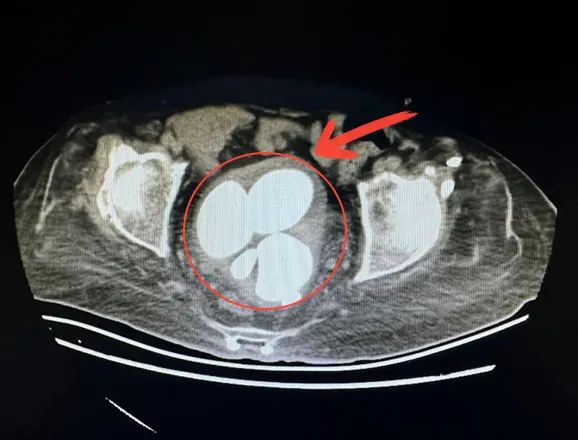

近日,晉城大醫(yī)院泌尿外科完成一例罕見巨大膀胱結(jié)石切開取石手術,結(jié)石已長滿膀胱,直徑超過7cm的就有4枚,最大的竟有鴨蛋大小。

吳師傅30余年前因外傷導致雙下肢截癱,無法自行排尿,長期臥病在床,依靠尿管排尿。近一周以來,吳師傅感覺下腹部反復疼痛,隨即來晉城大醫(yī)院泌尿外科就診。入院完善檢查后,結(jié)果讓人難以想象,吳師傅膀胱內(nèi)長滿了大大小小的結(jié)石,最大的直徑已經(jīng)超過7cm。

考慮到膀胱結(jié)石巨大,如采用微創(chuàng)手術,雖然體表無傷口,但是碎石時間太長,反倒引起更多并發(fā)癥。經(jīng)與患者家屬充分溝通后,泌尿外科主任畢慧鋒團隊決定采取膀胱切開取石術。在麻醉手術團隊的通力協(xié)作下,很快將一枚枚巨大結(jié)石順利取出,結(jié)石總重量驚人,達到450g。目前患者恢復良好。